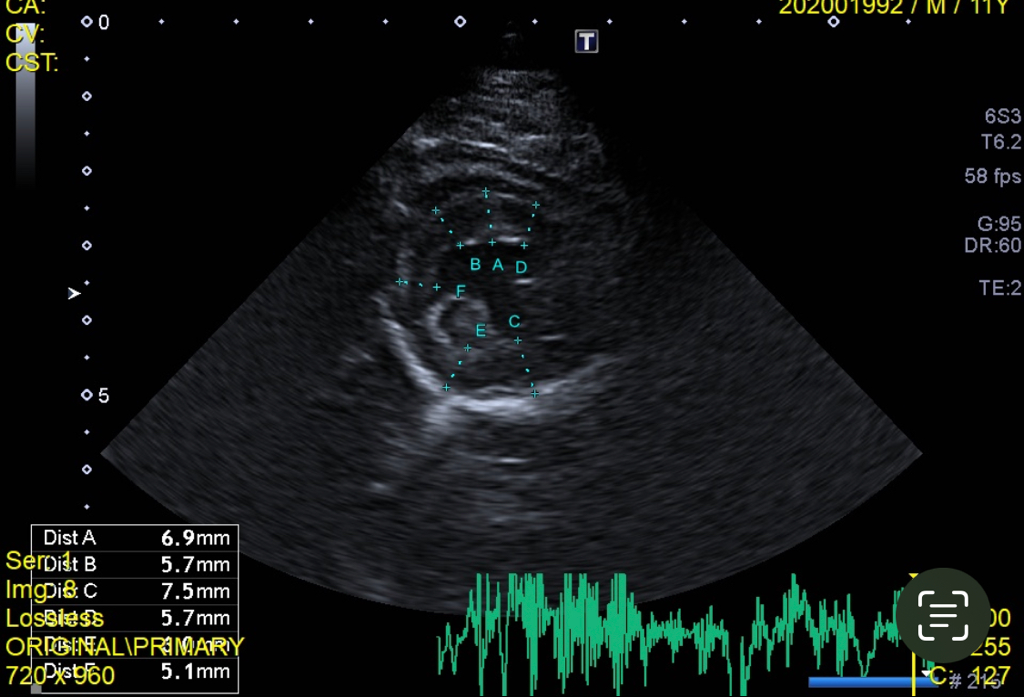

재검진 받았는데 심장 초음파시 가장 얇은 두께 5.1mm 두꺼운 건 7.5mm 가 나왔습니다 NT-pro 수치는 400초반이구요 b2초기로 약을 먹어야 될거같다고 12시간 간격으로 먹는 약이랑 혈전제포함된 저녁약을 주셨는데 심장병이 맞는지 모르겠습니다 3개월 보다 더 두꺼워진 것과 수치가 정상이 아닌 점을 고려하면 맞을까요? ucm 심장병이라고 진단받았습니다